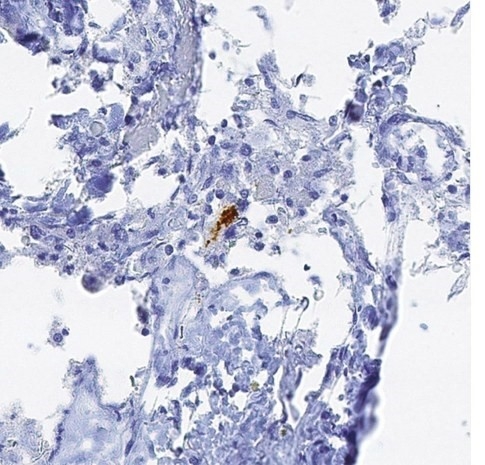

La investigación descubrió la proteína del Alzheimer en el cerebro de siete de ocho pacientes que habían muerto de la enfermedad de Creutzfeldt-Jakob (ECJ), otra dolencia cerebral, que es causada por una proteína llamada prión.

Los pacientes habían contraído la ECJ en tratamientos con hormona para el crecimiento contaminada y las autopsias mostraron que sus cerebros tenían además niveles significativos de la proteína Beta-amiloide, relacionada con la formación de placas que se da en pacientes con Alzheimer.

Ese hallazgo sugirió que las personas tratadas con la hormona del crecimiento humano en el pasado y actualmente podrían estar en peligro no sólo de desarrollar ECJ sino también Alzheimer por una transmisión médica accidental de la proteína amiloide, dijo Collinge.